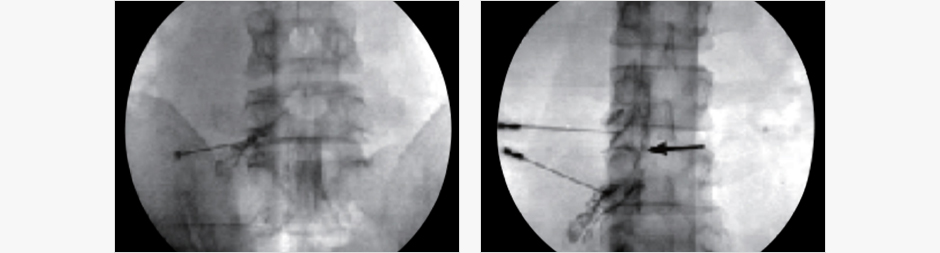

주사 방법

- 시술 시간은 10분 정도 걸립니다

- 투시경을 이용하여 화면으로 보며 신경주위까지 바늘을 넣어 주사합니다.

- 회복실에서 5~10분 정도의 안정을 취한 후에 퇴원합니다.

- 대개 주사는 환자의 증상에 따라 1~2주 간격으로 맞으며 3회 정도까지 시행합니다.

- 증상의 정도에 따라 추가적으로 시행할 수 있습니다